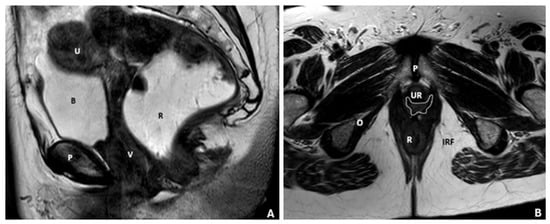

| Pelvic Compartment | Contained Organs | Supportive Structures | Condition | Measurement Method | Grading Criteria |

|---|---|---|---|---|---|

| Anterior | Urinary bladder, urethra | Pubocervical fascia (part of endopelvic fascia) | Cystocele (bladder descent) | Bladder neck position relative to PCL | Mild: 1–3 cm, Moderate: 3–6 cm Severe: >6 cm |

| Middle | Vagina, cervix, uterus | Paracolpium, parametrium (endopelvic fascia) | Uterine descent | Uterine fundus position below PCL | Mild: 1–3 cm Moderate: 3–6 cm Severe: >6 cm |

| Vaginal descent | Vaginal fornix position relative to PCL | Mild: 1–3 cm Moderate: 3–6 cm Severe: >6 cm | |||

| Posterior | Colon | Enterocele, sigmoidocele, peritoneocele | Position below the posterior cervicovaginal ligament | Mild: 1–3 cm Moderate: 3–6 cm Severe: >6 cm | |

| Rectum, anal canal | Rectovaginal fascia, perineal body | Rectal intussusception/prolapse | Extent of rectal mucosa relative to rectocele/anal canal | Mild: 1–2 cm Moderate: 2–4 cm Severe: >4 cm |